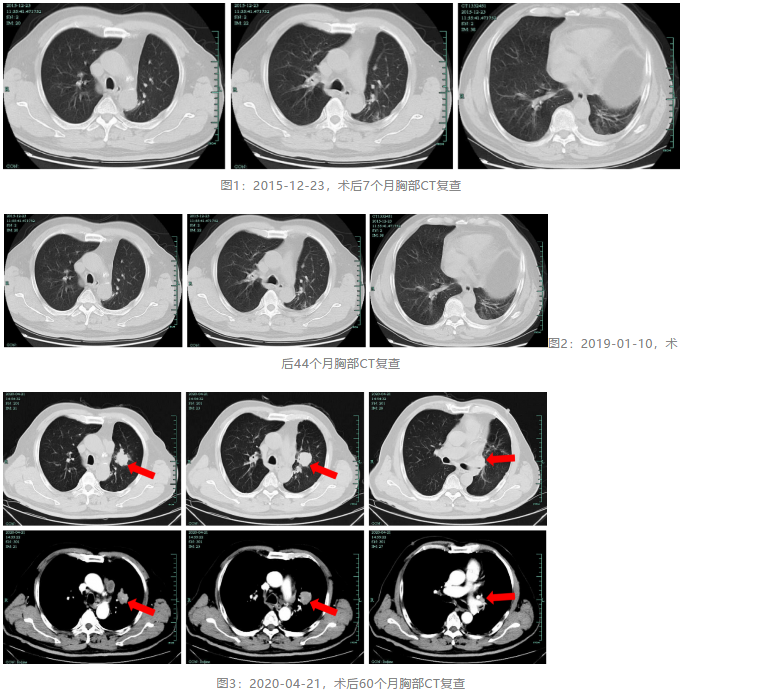

现病史:患者于2015年5月行左下肺癌根治术,术后病理提示周围型低分化鳞癌,pT1bN0M0,大小约3×2.7 cm,术后曾行4次多西他赛+顺铂化疗,一直定期复查肺部CT,无复发依据。患者术后肺功能:极重度阻塞性通气功能障碍,长期吸入沙美特罗替卡松、噻托溴铵治疗。2019年12月23日复查,发现左肺上叶结节灶,伴淋巴结肿大,当时无症状,患者暂拒进一步治疗。2020年4月2日,患者因咳嗽、活动后气急加重,为求进一步治疗来诊。

胸部CT(2020-04-26):左肺上叶结节灶,伴淋巴结肿大。